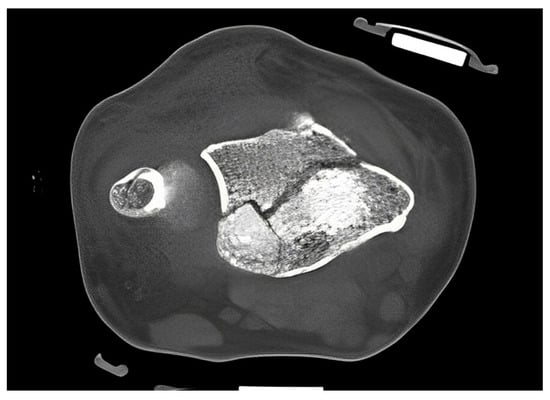

The standard treatment approach in our Level I trauma center was not altered by the study protocol, except from the placement of the orthosis. In our approach, we were able to adjust the orthosis used immediately during finger-trap traction and show that there was no increase in secondary dislocations on the radiographic and CT control imaging and, moreover, that diagnostic procedures were in no way restricted when the orthosis was in place. The quality of detail was not limited in any way in the lateral projection, very less in the posteroanterior view (Figure 6A–D). Additionally, the use of the orthosis did not affect the CT scan. As shown in Figure 7, there are no metal artifacts induced by the aluminum splints. Hence, modern orthoses enable comprehensive radiographic diagnostics.

Figure 7.

CT scan of a DRF in transversal view. The use of aluminum-based orthosis does not induce metal artifacts.